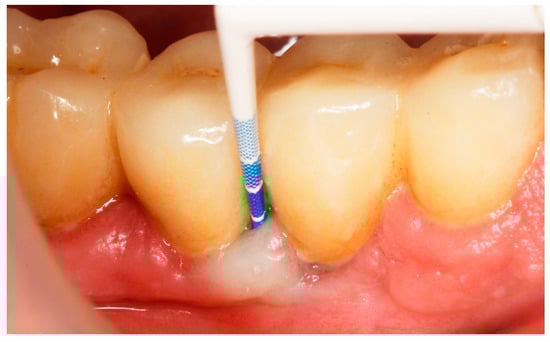

2.8. Treatment Procedures

- PMPR, individualized OH recommendations, for entire dentition/implants;

2.9. Evaluation of Treatment Effect